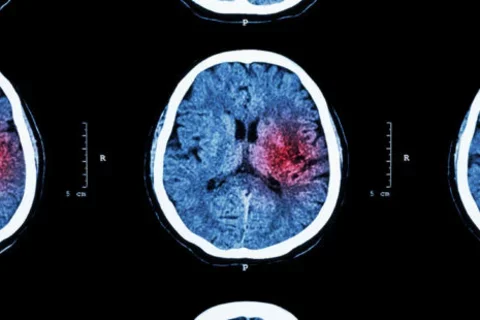

Some coronavirus patients may suffer from ‘micro-strokes’ that are too small to notice

Nate Favini (Medical Lead, Forward Health and UCLA RWJF CSP Alumni), in a recent article, discusses patients of COVID-19 suffering from micro-strokes.